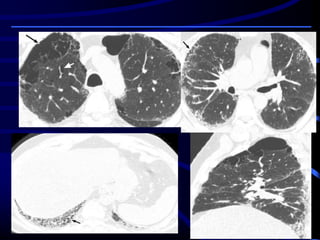

Diagnostic Approach to Patients with SR-ILDs

An integrated clinical, radiologic, and pathologic approach to the

diagnosis of SR-ILD is recommended, as with other diffuse

parenchymal lung diseases . The diagnostic process begins with a

clinical evaluation that includes history, physical examination,

chest radiography, and pulmonary function tests. High-resolution

CT plays an integral role in evaluation. In the appropriate clinical

context, the presence of typical changes at high-resolution CT,

such as nodules and cysts in PLCH and honeycombing and

emphysema in smoking-related IPF, renders the diagnosis almost

certain and may obviate further testing. Surgical lung biopsy is

indicated when the findings at high-resolution CT are relatively

nonspecific, as in RB-ILD and DIP, or when a confident definitive

diagnosis is needed.